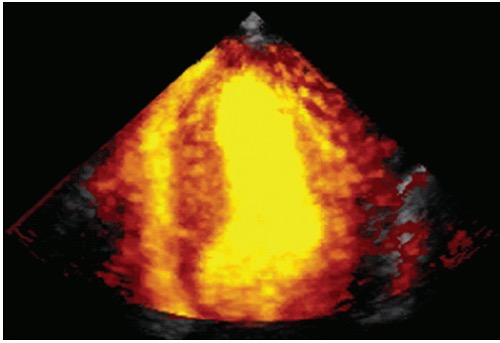

- Power Doppler image recorded at the time of contrast echocardiography using a perfluorocarbon-based agent. Note the excellent signal-to-noise ratio and the marked discrimination between the blood pool and the wall with this imaging method.

使用基于全氟化碳的试剂进行对比超声心动图时记录的功率多普勒图像。注意这种成像方法的出色信噪比和血池与血管壁之间的明显区别。

Perfusion studies

心肌灌注研究![Perfusion - 左室室腔呈现黄色,左室室壁呈现橘红色的点状成像,在心尖箭头处可以看到呈现黑色的部分,这是没有充盈增强剂的表现,说明局部室壁有变薄,有疤痕形成,局部血供是降低的]()